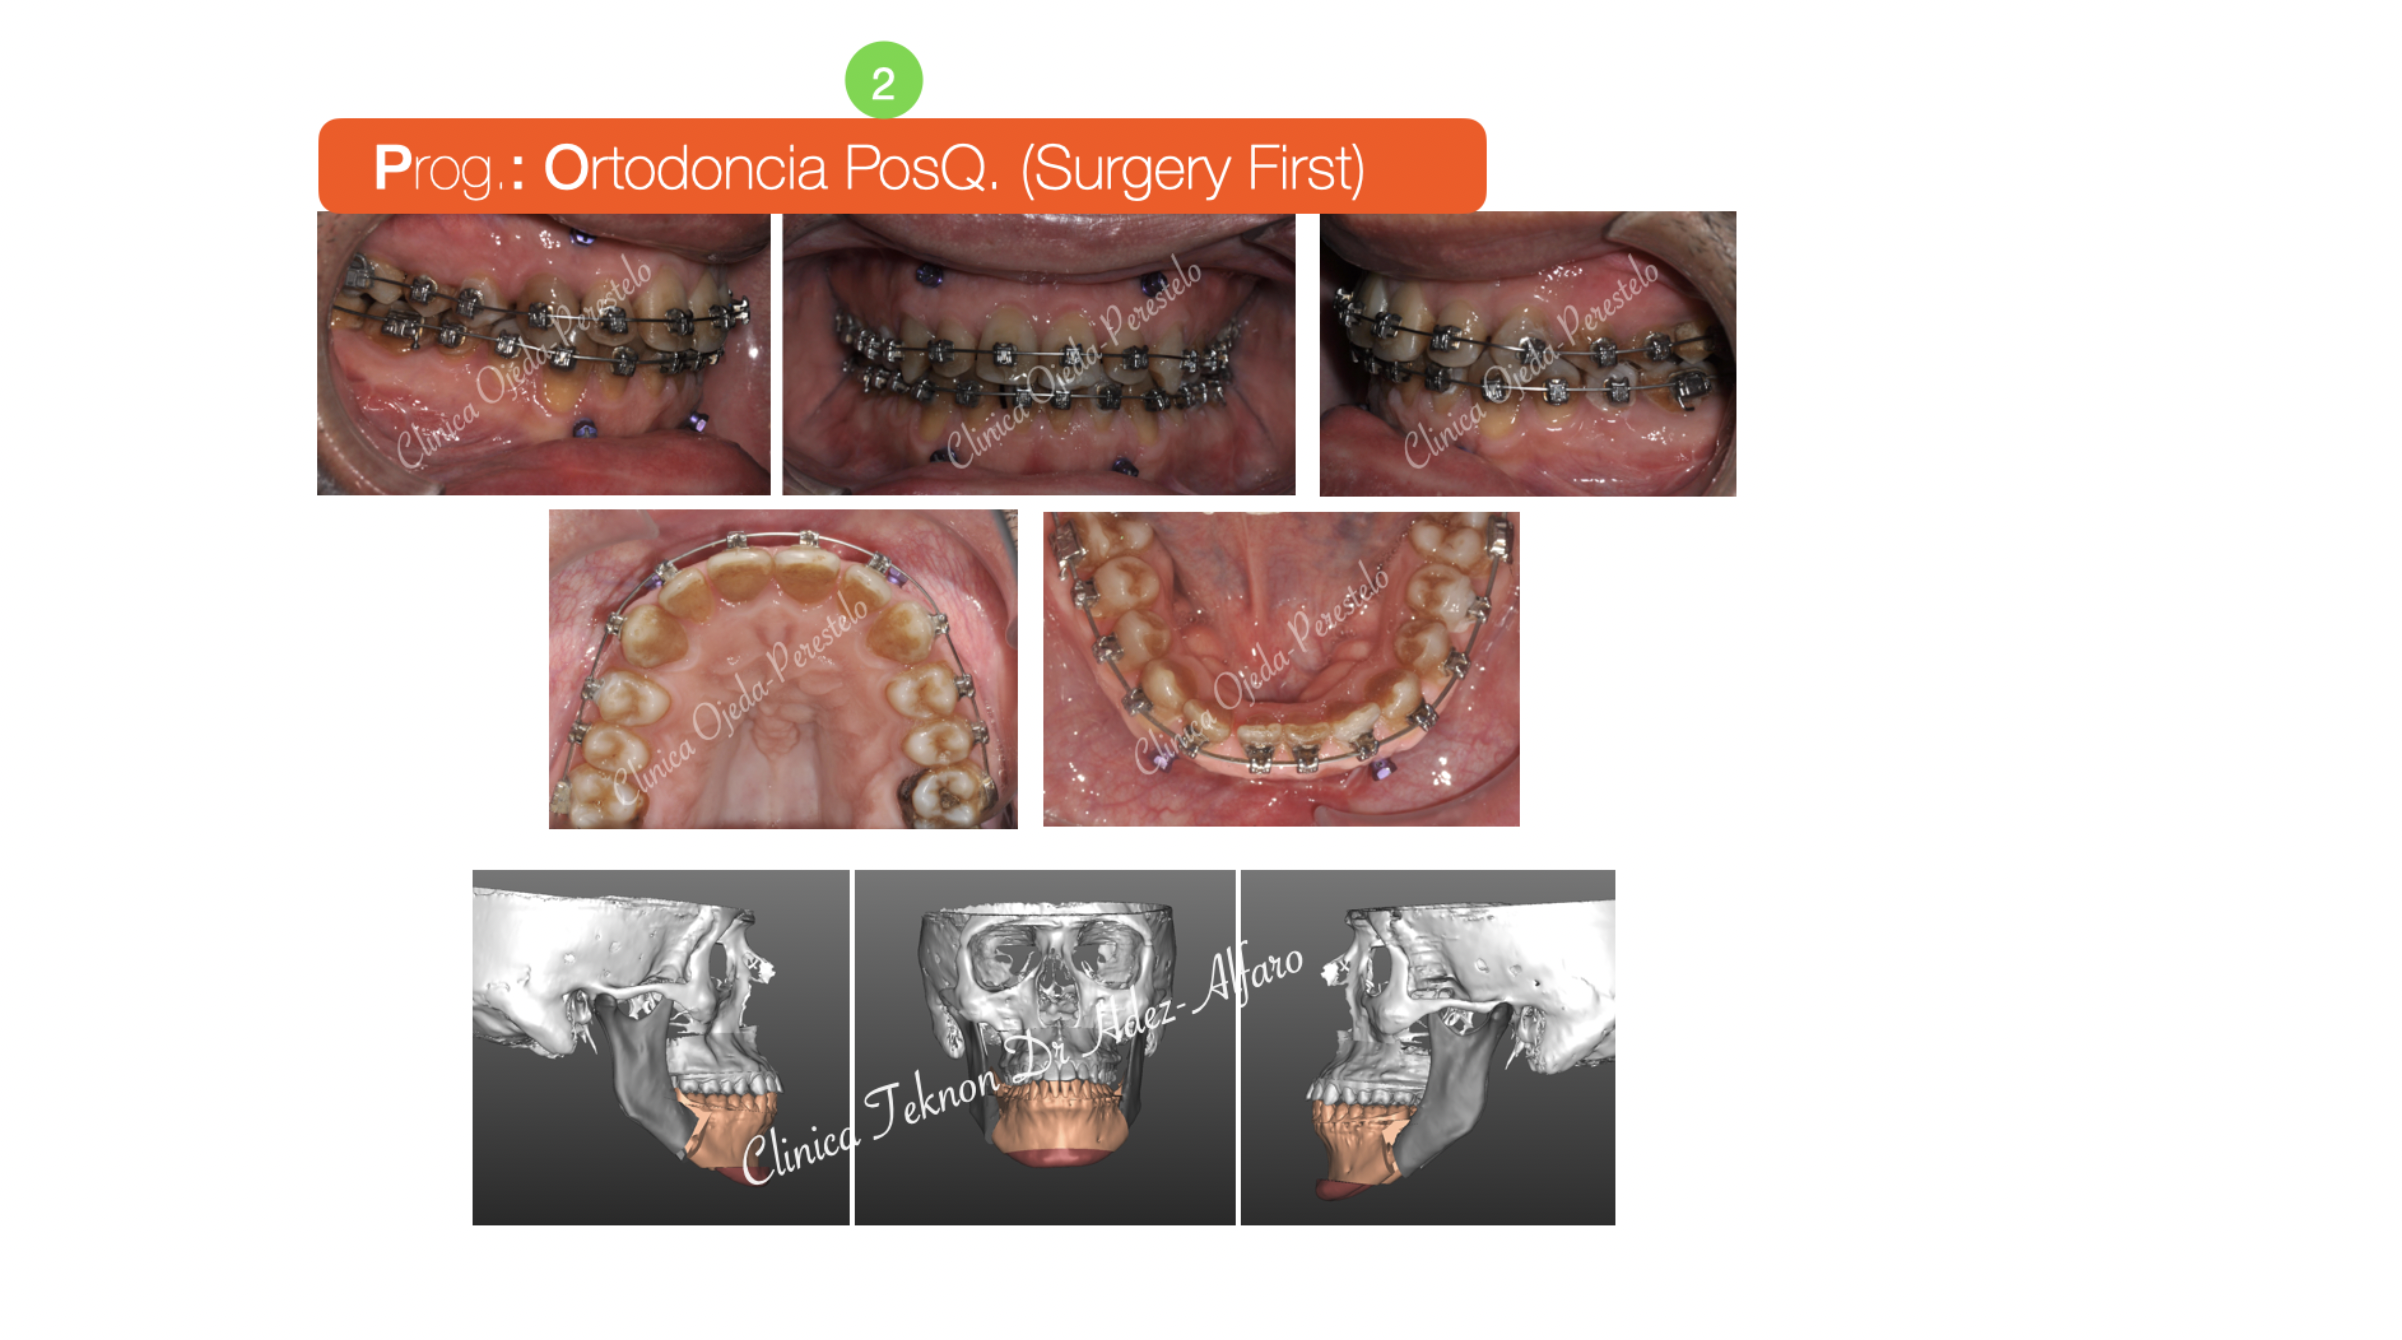

Biprotusión esquelética con Sonrisa Gingival

Paciente que consulta porque no le gusta su muy prominente sonrisa que le dificulta mantener la boca cerrada. El paciente quiere mejorar su aspecto facial así como el exceso de encías al sonreír (sonrisa gingival). Presenta un ordenamiento natural de sus piezas que nos permite comenzar con la intervención de Cirugía Ortognática desde un primer momento (Surgery First).

La intervención es realizada por el equipo del Dr Hdez-Alfaro y fue planificada con Lefort para Impactación y Retrusión del Maxilar conjuntamente con Osteotomia Sagital de Rama para centrado y retrusión Mandibular con Mentoplastia. Quisiera destacar la eliminación de la sonrisa gingival y la mejoría en la armonía facial y la permeabilidad de la vía Aérea.